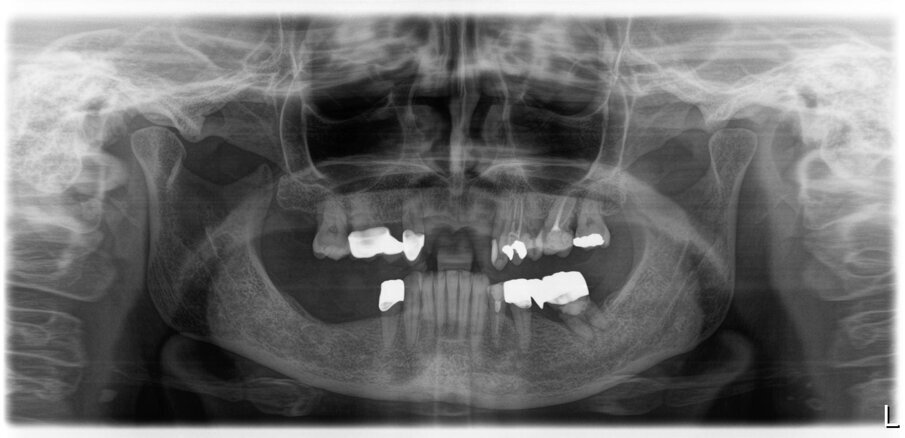

Nell’arcata inferiore dopo il trattamento parodontale abbiamo mantenuto inalterato il V° sestante provvedendo alla rimozione del 3.7 mesio-inclinato con sondaggio e mobilità difficilmente recuperabili e sostituendolo con un impianto. La scelta implantare poco convenzionale ha previsto per la sostituzione bilaterale dei diatorici con impianti in titanio di differente forma e connessione, inserendo bone level (BL) sui premolari e tissue level (TL) sui molari con una protesizzazione mista. La scelta del BL o del TL era rivolta a un aspetto estetico sui premolari e di maggior rispetto tessutale sui molari. Durante le fasi di prova (Fig. 41) si valutano le compressioni dei tragitti transmucosi (Fig. 42), gli eventuali precontatti, si finalizzano le forme e si rileva nuovamente il colore secondo la tecnica di depolarizzazione (Fig. 43). L’appuntamento successivo sancisce l’ottimizzazione dei restauri (Figg. 44, 45). Dopo il posizionamento definitivo dei restauri protesici e l’ottimizzazione dei contatti (Fig. 46) viene nuovamente registrato l’equilibrio di masticazione tramite l’uso del sincronogiografo che registra le forze muscolari confrontando i valori registrati dal momento iniziale pre-trattamento a quello con i provvisori e infine alla stabilizzazione finale, così che nel tempo si possa aver traccia dell’adattamento realizzato (Fig. 47). Il recupero funzionale ed estetico (Figg. 48, 49) rappresentano il traguardo dopo un lungo percorso. Il condizionamento della paziente ha rappresentato un ostacolo nelle libere scelte cliniche segnando di conseguenza l’intero percorso. L’aspetto psicologico ha giocato un ruolo importante nella realizzazione del piano di trattamento, la malattia precedente e il lungo periodo di provvisorizzazione ha arrecato nella paziente un forte disagio. Talvolta quest’aspetto induce il clinico a fare dei compromessi procedurali e anche noi abbiamo cercato di ottimizzare una riabilitazione estetico funzionale correndo dei rischi procedurali a fronte di una richiesta conservativa e talvolta riduttiva nelle procedure chirurgiche. A oggi il follow-up e i controlli di igiene e di verifica della funzione è cadenzato e rigorosamente rispettato dalla paziente. A 5 anni non sono stati evidenziati problemi dei materiali impiegati né tantomeno funzionali (Figg. 50, 51).

Fig. 50_Radiografia iniziale

Fig. 51_Radiografia a 5 anni dalla consegna del lavoro. Ai follow-up vengono eseguite annualmente delle rx endorali centrate, e alla necessita viene ripetuta un’opt.